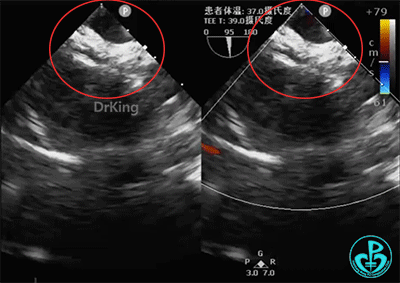

成型锁定

钢缆和鞘管轻轻抵住房间隔,固定钢缆和鞘管并牵拉成型线锁定,超声下观察封堵器形态,封堵器呈工字形稳定骑跨于房间隔两侧,成型良好。